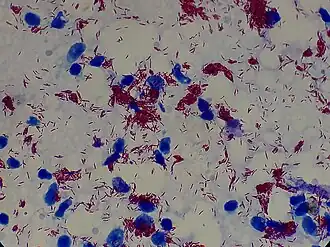

Mycobacterioum leprae and Mycobacterium lepromatosis are the mycobacteria that cause leprosy.[29] M. lepromatosis is a relatively newly identified mycobacterium isolated from a fatal case of diffuse lepromatous leprosy in 2008.[5][30] M. lepromatosis is indistinguishable clinically from M. leprae.[31] M. leprae is an aerobic, rod-shaped, acid-fast bacterium with a waxy cell envelope characteristic of the genus Mycobacterium.[32] M. leprae and M. lepromatosis are obligate intracellular pathogens and cannot grow or be cultured outside of host tissues.[5][33] However, they can be grown using research animals such as mice and armadillos.[34][35]